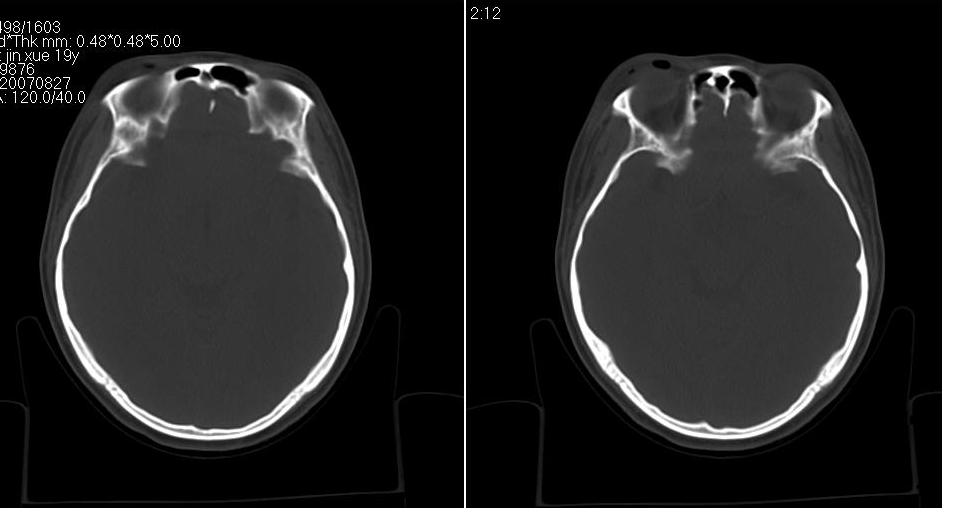

标题: CT9542:鼻窦CT平扫 [打印本页]

标题: CT9542:鼻窦CT平扫

女 18岁,外伤.

右侧上颌窦前壁骨折,窦腔积液.

右侧上颌窦前后壁及右颧骨弓骨折,窦腔积液。

右侧上颌窦前后壁骨质均不连续,窦腔内见一致性高密度影,右睑部软组织肿胀

1,右上颌窦前后壁骨折,伴窦腔积血可能性大

2,右睑部软组织肿胀

右侧上颌窦前后壁及颧弓骨质均不连续,窦腔内见一致性高密度影,右面部及眼睑部软组织肿胀

1,右上颌窦前后壁骨折伴窦腔积血,右侧颧弓骨折.

2,右面部及眼睑部软组织肿胀